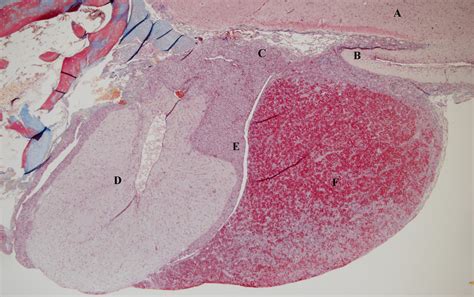

The pituitary gland is located at the base of the brain, within a bony structure called the sella turcica. It is divided into two main parts: the anterior pituitary (adenohypophysis) and the posterior pituitary (neurohypophysis). The infundibular stalk, also known as the pituitary stalk, connects the pituitary gland to the hypothalamus. This stalk is composed of both neural and vascular elements, allowing for the bidirectional communication between the hypothalamus and the pituitary gland.

• Supportive tissue: Glial cells and other supportive structures that maintain the integrity of the stalk.